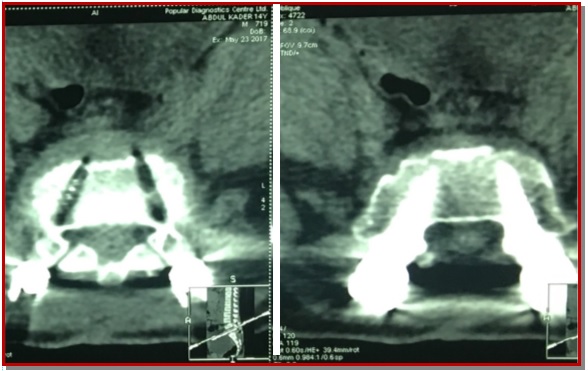

Spondylolisthesis is forward slipping of upper vertebra in relations to its lower one, commonest is L4-L5. The ideal surgical treatment of spondylolisthesis is still controversial. Posterior lumber interbody fusion with pedicle fixation is one of treatment choices for the lumber spondylolisthesis. Forty patients who operated through posterior lumber interbody fusion and pedicle screw fixation by single surgeon was included from January 2012 to March 2015. Periodical follow-up was done both clinically and radiologically up to 6 months. Patient outcome was completed based on pain relief graphic rating scale and Oswestry disability index. In our series, the excellent outcome were 25 patients (62.5%), good were 12 patients (30%), and fair were 3 patients (7.5%). There were no poor outcome and no new neurological deficit. This study concludes that posterior lumber inter-body fusion with pedicle is an effective treatment for the lumber spondylolisthesis. It helps to maintain the biomechanics, associated with less complication and improve the quality of life of patient.